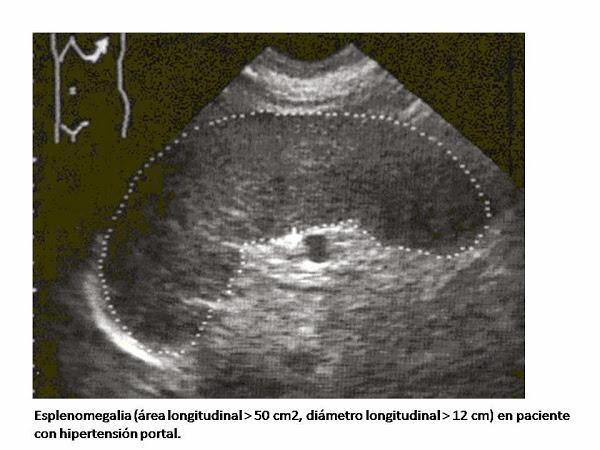

La esplenomegalia es un aumento patológico del tamaño del bazo más allá de sus dimensiones normales (11 cm). El peso normal del bazo en un adulto es de 80-200 gramos en los hombres, y 70-180 gramos en las mujeres, con un promedio de 150 gramos. El bazo es clínicamente palpable cuando aumenta su tamaño un 40% del valor basal.Se ha demostrado una baja sensibilidad de las maniobras semiológicas para la valoración de la esplenomegalia, presentando además una amplia variabilidad interexplorador, por lo que el método Gold Standard para el diagnostico de esplenomegalia lo constituye la ecografía, considerándose esplenomegalia un diámetro del bazo mayor de 13 cm, aunque hay que saber que también la ecografía es una técnica con una gran variabilidad interexplorador.

El TAC de abdomen permite una estimación precisa del tamaño del bazo, y no está influenciada por el ecografista, considerándose esplenomegalia si el diámetro mayor del bazo es mayor de 10 cm, sin embargo tiene el inconveniente del mayor coste que la ecografía.

La evaluación por ecografía puede confirmar la presencia de esplenomegalia o quistes, tumores, abscesos, hematomas, mide el tamaño real del bazo. Además puede confirmar lesiones hepáticas, adenopatías, etc.Otras exploraciones complementarias: